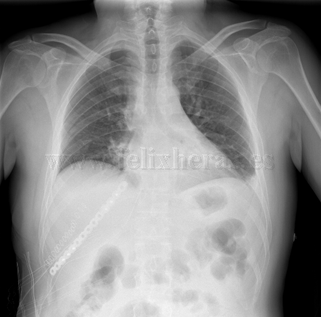

Osteosíntesis costal